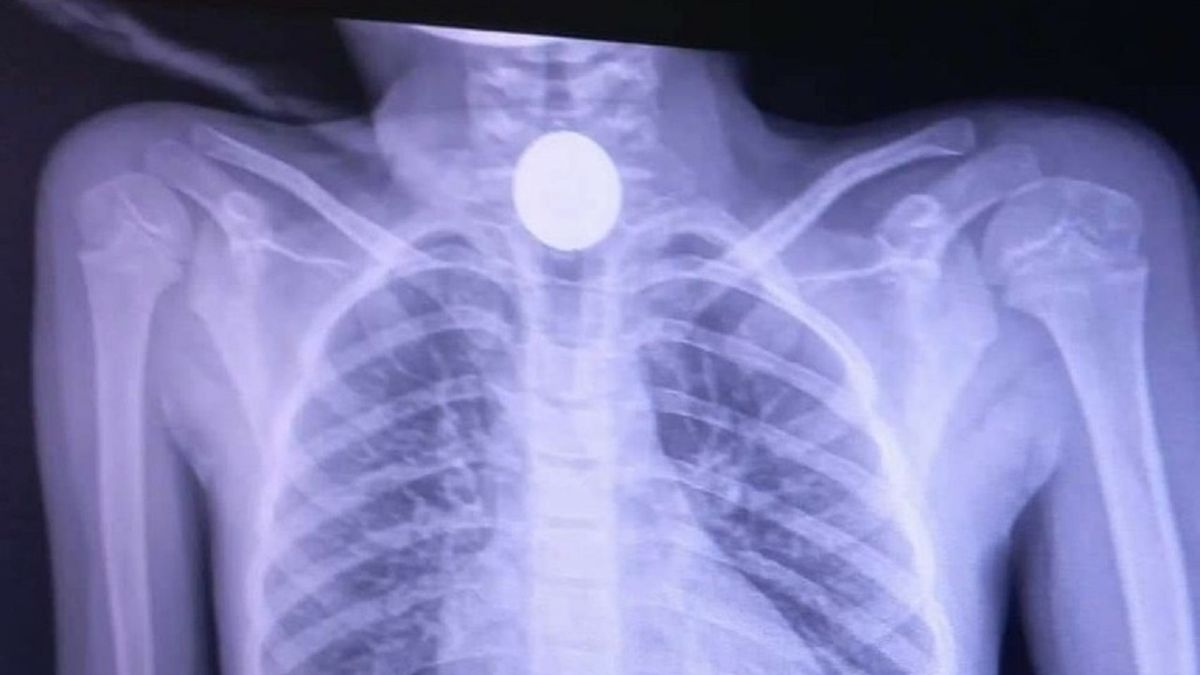

Zdjęcie rentgenowskie 6-letniej dziewczynkiZdjęcie rentgenowskie 6-letniej dziewczynki

Źródło zdjęć: © Wojewódzki Szpital w Przemyślu | Wojewódzki Szpital w Przemyślu

Zdjęcie rentgenowskie wyraźnie uwidoczniło miejsce, gdzie zatrzymała się moneta. Konieczny był zabieg ezofagoskopii. Polegał on na tym, że przez usta lekarz wprowadził sztywny wziernik i specjalnymi kleszczykami wyciągnął przedmiot. Procedurę wykonuje się w znieczuleniu ogólnym. Na szczęście wszystko dobrze się skończyło i pacjentka już następnego dnia została wypisana do domu - poinformował rzecznik szpitala, Paweł Bugira, w rozmowie z portalem Nowiny24.